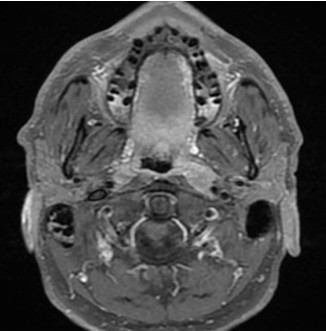

Vous recevez en consultation un patient de 54 ans présentant une gêne pharyngée depuis plus de trois semaines. Il a pour antécédents un tabagisme sevré à 15 paquets-années sans intoxication éthylique avouée ni exposition professionnelle connue. Le patient est adressé en consultation oto-rhino-laryngologique après un traitement par amoxicilline 1 gramme trois fois par jour pour une durée de 7 jours sans régression de la symptomatologie et deux consultations médicales. A l’examen clinique, on ne palpe pas d’adénomégalie cervicale, l’examen de la cavité buccale (fig.1) retrouve une érosion superficielle à la jonction voile du palais, pôle supérieur de l’amygdale gauche de 15 millimètres de grand axe légèrement indurée à la palpation.

Fig.1 : Lésion érosive à la jonction voile du palais et pôle supérieur de l’amygdale gauche de 15 mm de grand axe